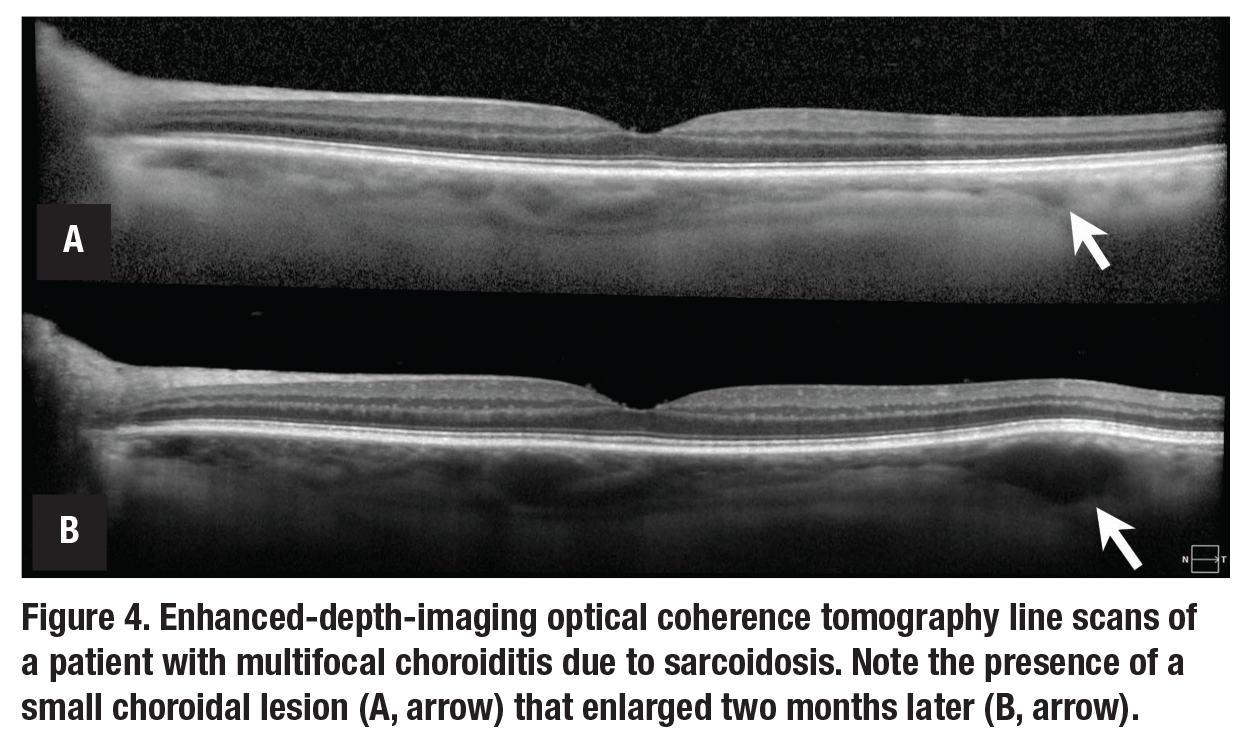

Many uveitides feature a multifocal rather than diffuse choroiditis. In eyes with extensive choroidal lesions, monitoring for the development of new lesions can be cumbersome. Lesions may not be readily evident on ophthalmoscopy, may rely on

indocyanine green angiography and may not always correspond with other markers of disease activity. EDI-OCT can allow for the monitoring of new macular and peripapillary choroidal lesions and the response of such lesions to therapy (Figure 4).15